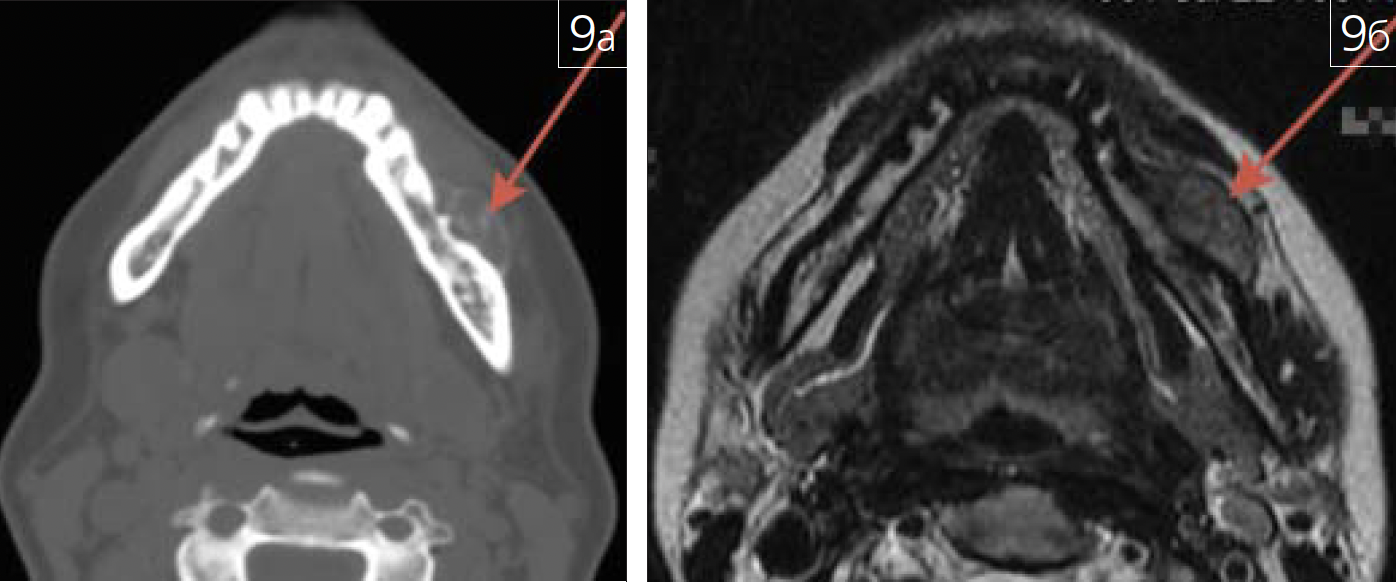

Патология костной ткани может характеризоваться не только изменением ее структуры, но и изменениями прилежащих мягких тканей (рис. 9 а-в).

Рис. 9. Центральнаягигантоклеточная репаративнаягранулёма нижней челюстислева (зона патологическихизменений отмечена нарисунках красной стрелкой):а – аксиальная проекция МСКТ;б – аксиальная проекция МРТ,Т2 ВИ;

Рис. 9. Центральнаягигантоклеточная репаративнаягранулёма нижней челюстислева (зона патологическихизменений отмечена нарисунках красной стрелкой): в – гистологическийпрепарат опухоли, окрашенныйгематоксилином и эозином,увеличение 200:1